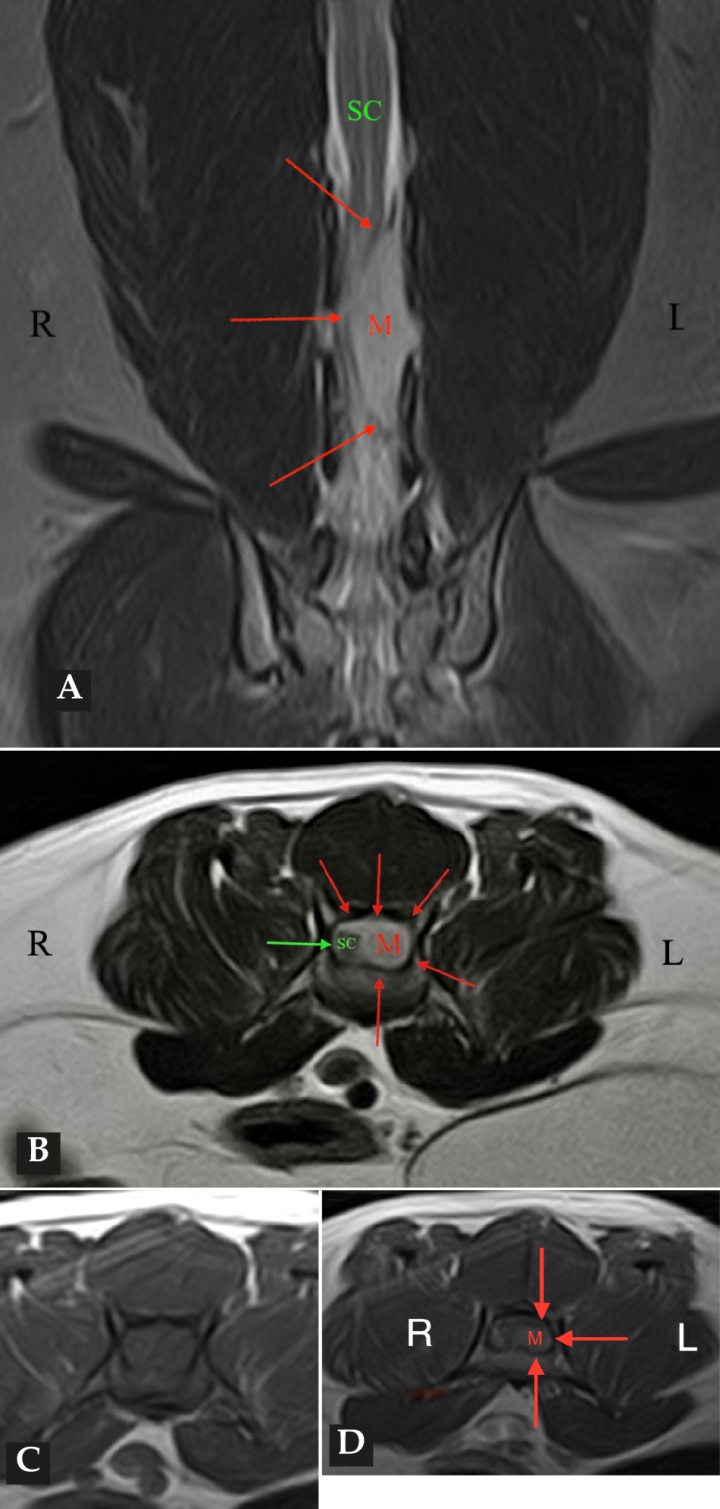

Las pruebas diagnósticas realizadas incluyeron análisis de sangre, radiografía laterolateral de tórax y ecografía abdominal, sin resultar en alteraciones significativas. La serología frente al virus de la leucemia e inmunodeficiencia felina resultó positiva para esta última. En el estudio de resonancia magnética (RM; Fig. 2) de la región toracolumbosacra (Toshiba Vantage Elan 1.5 T: Adquisición de planos transversal, sagital y coronal ponderados en T1 pre y post-contraste intravenoso con gadolinio, así como planos ponderados en T2 y STIR) se cuentan 6 vértebras lumbares, lo cual es compatible con anatomía de transición en la región lumbar, como hallazgo incidental. En el lado izquierdo del canal vertebral, desde el tercio craneal de la vértebra L5 hasta el tercio caudal de la vértebra L6 se encuentra una lesión con aspecto alargado y de base ancha, con márgenes mal definidos e irregulares, distribución posiblemente extradural y/o intradural/extramedular, causando compresión severa de la médula espinal, que aparece desplazada hacia el lado derecho. En cuanto al patrón de intensidad de la señal, este fue hiperintenso de forma homogénea en las secuencias ponderadas en T2 e isointenso en las secuencias ponderadas en T1, con un realce homogéneo y focal en la región media de la vértebra L6. La lesión se extiende parcialmente en el foramen intervertebral izquierdo entre las vértebras L5 y L6 y se aprecia siringomielia leve, que puede ser un proceso secundario a la compresión de la médula espinal por parte de la lesión, más caudalmente a nivel lumbar.

<p>Imágenes de RM postcontraste en las que se identifica una lesión de forma alargada y ancha en su base, con distribución posiblemente extradural y/o intradural/extramedular a nivel de la vértebra L6 (flechas rojas). (<strong>A</strong>) Secuencia dorsal en STIR. (<strong>B</strong>) Secuencia transversal en T2. Nótese la compresión severa a la que es sometida la médula espinal (flecha verde). (<strong>C</strong>) Secuencia transversal en T1 precontraste. (<strong>D</strong>) Secuencia transversal en T1 postcontraste. M: masa; SC: médula espinal; R: derecha; L: izquierda.</p>

Imágenes de RM postcontraste en las que se identifica una lesión de forma alargada y ancha en su base, con distribución posiblemente extradural y/o intradural/extramedular a nivel de la vértebra L6 (flechas rojas). (A) Secuencia dorsal en STIR. (B) Secuencia transversal en T2. Nótese la compresión severa a la que es sometida la médula espinal (flecha verde). (C) Secuencia transversal en T1 precontraste. (D) Secuencia transversal en T1 postcontraste. M: masa; SC: médula espinal; R: derecha; L: izquierda.